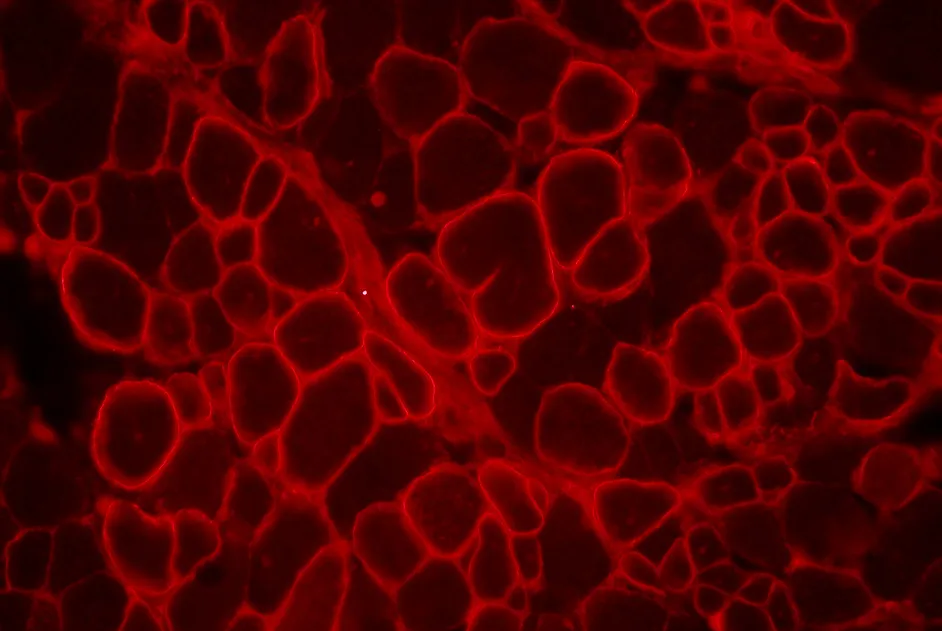

Le compte rendu du 193e workshop ENMC consacré au diagnostic anatomo-pathologique dans la myopathie inflammatoire idiopathique est paru en septembre 2013.

Identification de deux nouveaux cas de SMC lié à des mutations dans le gène MuSK chez lesquels la prise de salbutamol s’avère efficace.

Le compte rendu du 198e workshop ENMC, correspondant au 7e atelier exclusivement consacré aux myopathies centronucléaires, est paru en août 2013.

Identification d’un nouveau gène à l’origine d'une myopathie congénitale, le gène HACD1.

Une thérapie génique avec de nouveaux AAV-calpaïne 3 améliore les symptômes de souris modèles de LGMD2A sans être toxique pour leur cœur.

Un nouveau modèle de souris de la DMD a été développé pour étudier la transplantation de cellules souches musculaires à long terme.